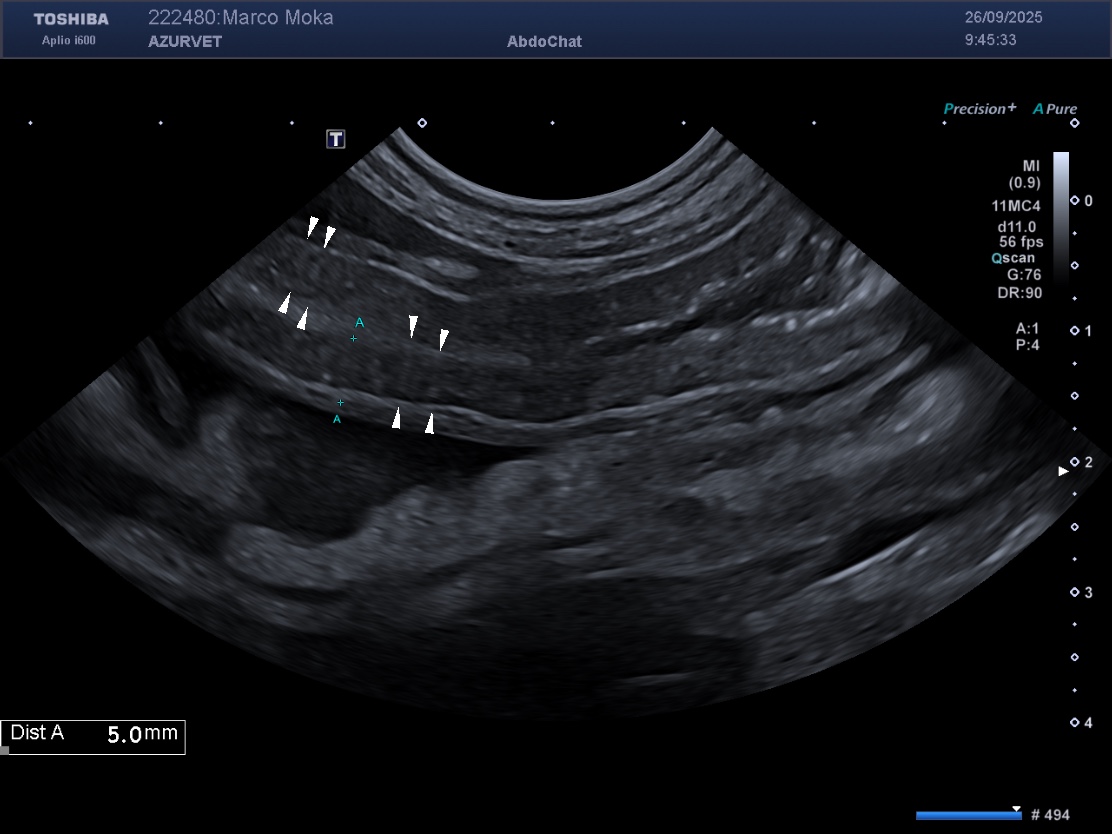

L’échographie est un examen de première intention pour l’exploration d’un insulinome. La sensibilité de l’échographie dépend de l’expérience du manipulateur, mais aussi de la conformation de l’animal (l’examen du pancréas est limité sur des chiens de grande taille et/ou avec cage thoracique profonde). Un insulinome peut se présenter dans la plupart des cas comme un nodule unique hypoéchogène de taille variable (figure 1), et de façon moins fréquente comme des nodules multiples ou une zone irrégulière plus diffuse du pancréas (2) – noter que ces lésions ne sont pas spécifiques d’un insulinome et que tout autre nodule bénin ou malin du pancréas peut avoir cette apparence et donc que la suspicion clinique/biologique est cruciale. L’échographie permet également une évaluation des nœuds lymphatiques et du foie pour un premier bilan d’extension.